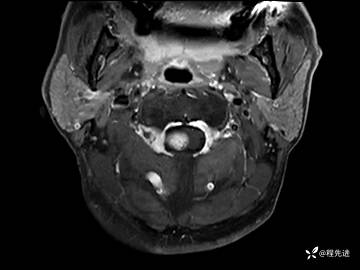

MRI平扫+增强:

T1增强: